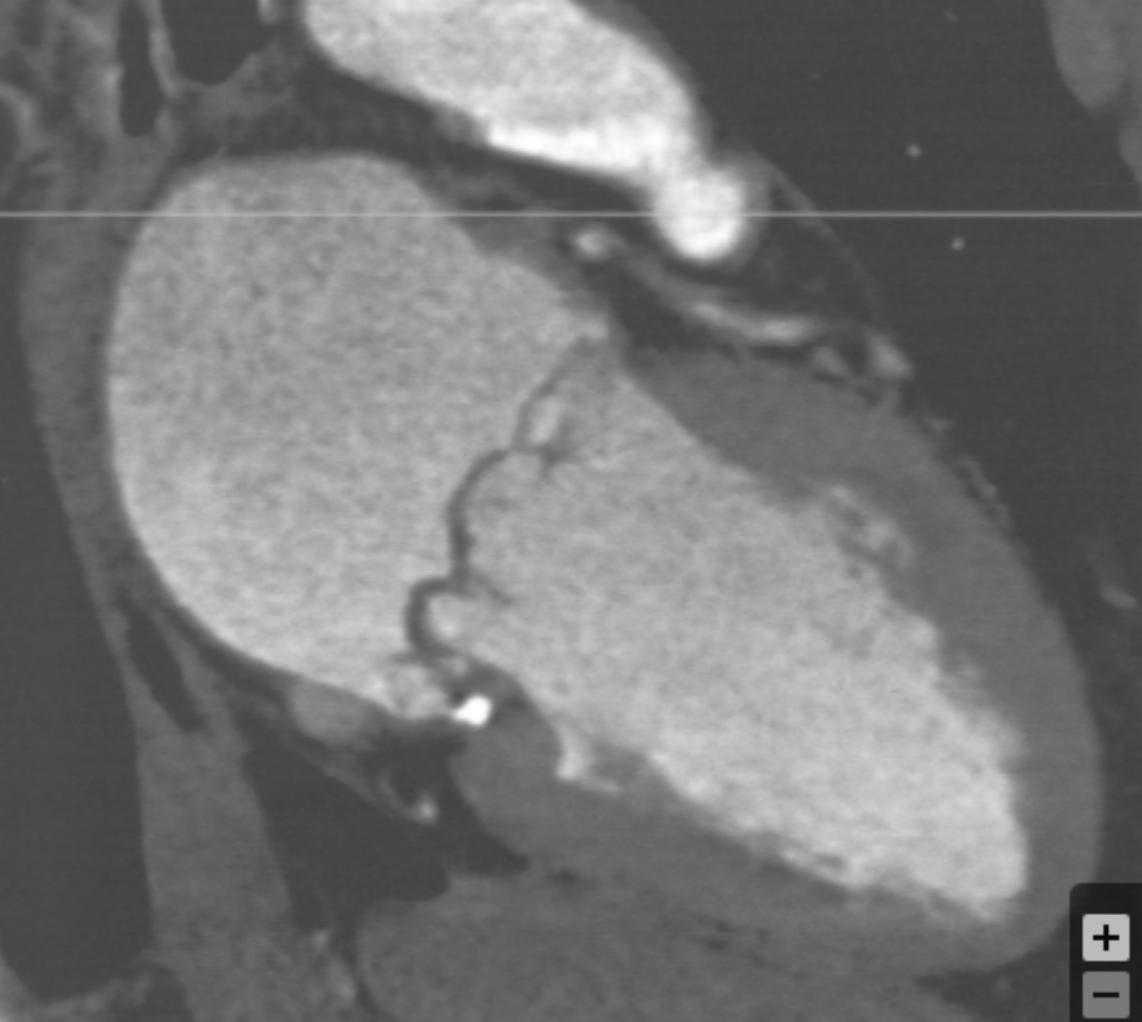

Describe the finding:

Microvascular obstruction